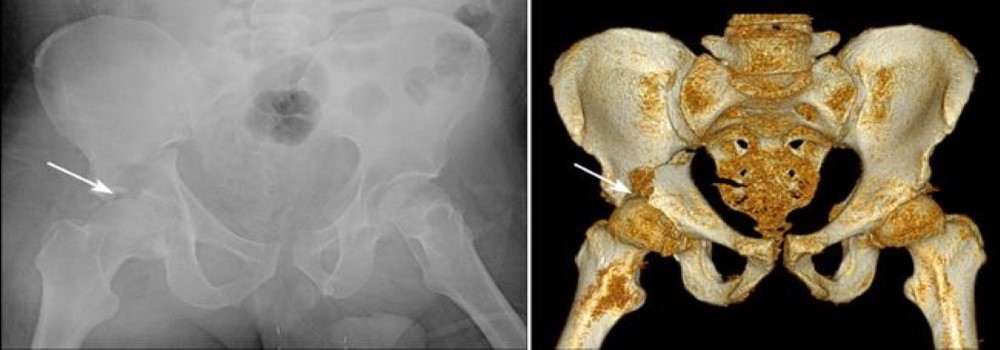

Computed tomography (CT) scan. Because of the complex anatomy of the pelvis, a CT scan is commonly ordered for acetabular fractures. The CT scan will provide your doctor with a more detailed, cross-sectional image of your hip and can be helpful in preoperative planning.

X-ray and 3-dimensional CT reconstruction of an acetabular fracture

(Left) This X-ray shows a fracture of the front "wall" of bone supporting the hip socket. (Right) The cracks and uneven surfaces of the same fracture are shown more clearly in this 3-dimensional CT reconstruction.